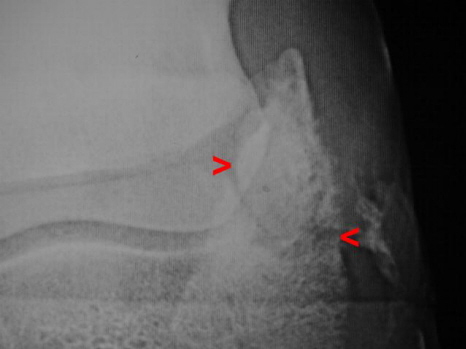

Hufbeinastfraktur